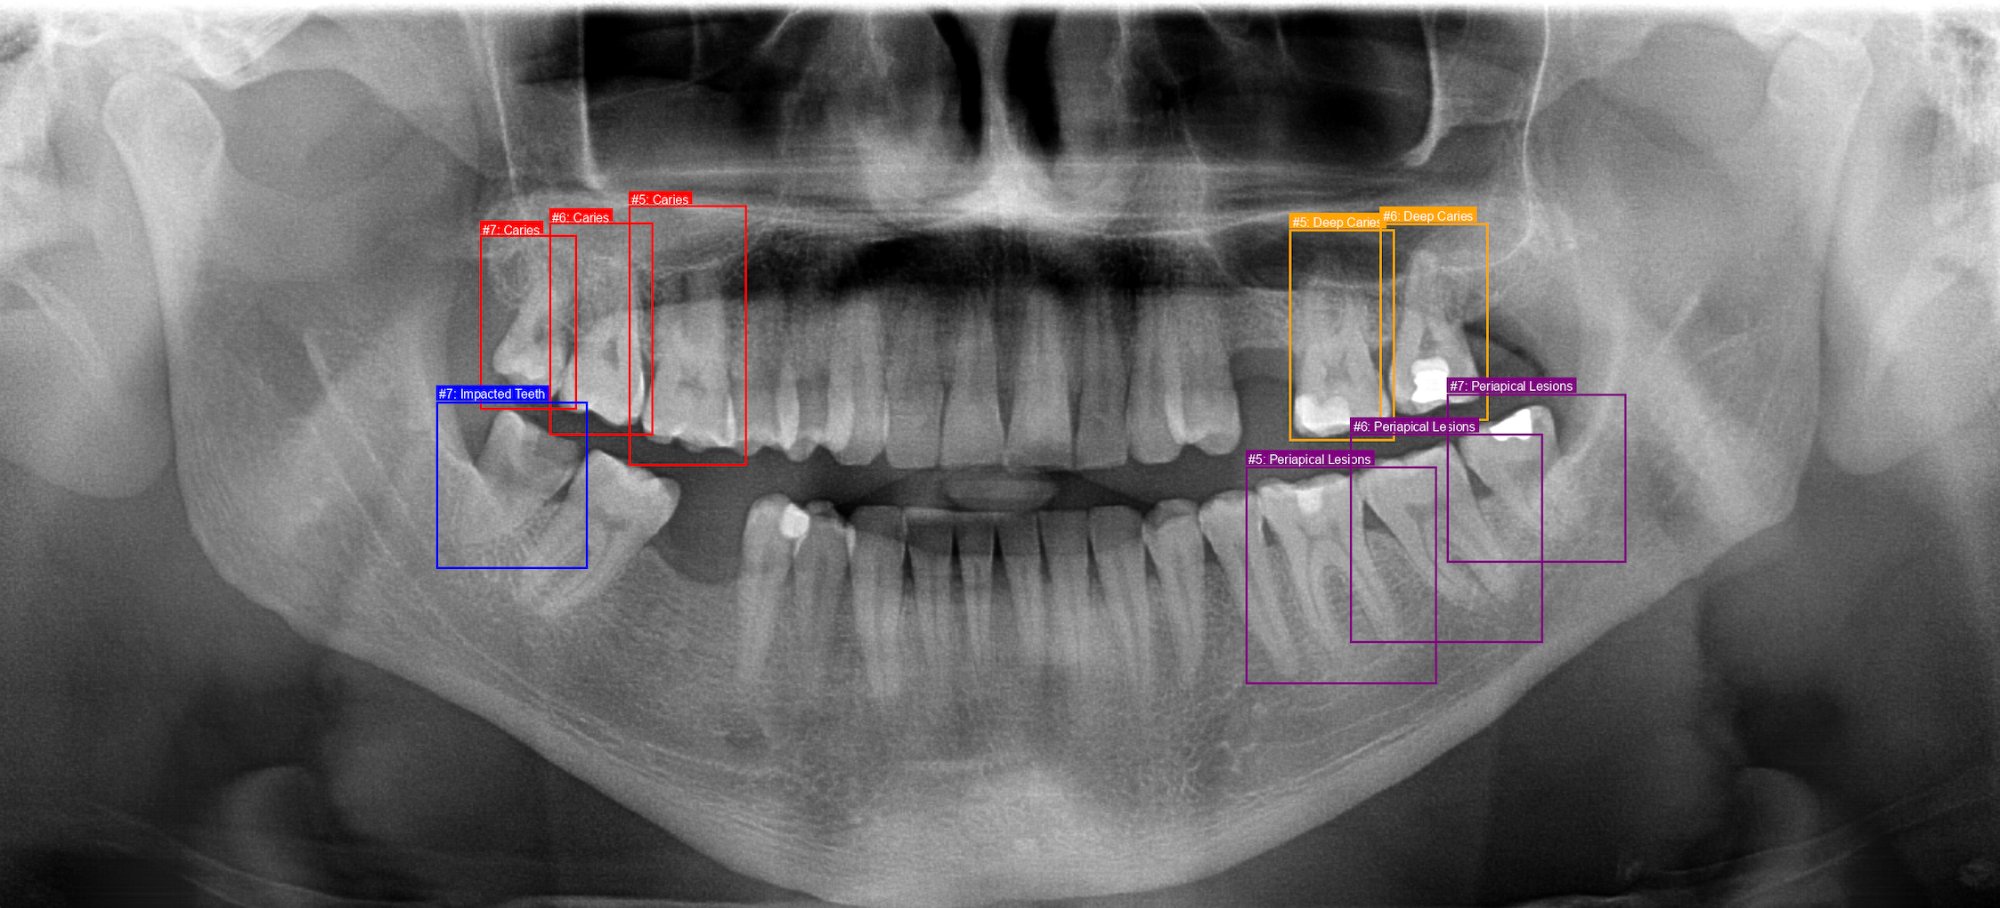

Annotated panoramic dental X-ray showing caries detection, impacted teeth identification, and periapical lesion detection with color-coded bounding boxes

Comprehensive annotation by licensed dentist—caries detection, impacted teeth identification, periapical lesions, and severity classification with precise bounding boxes.